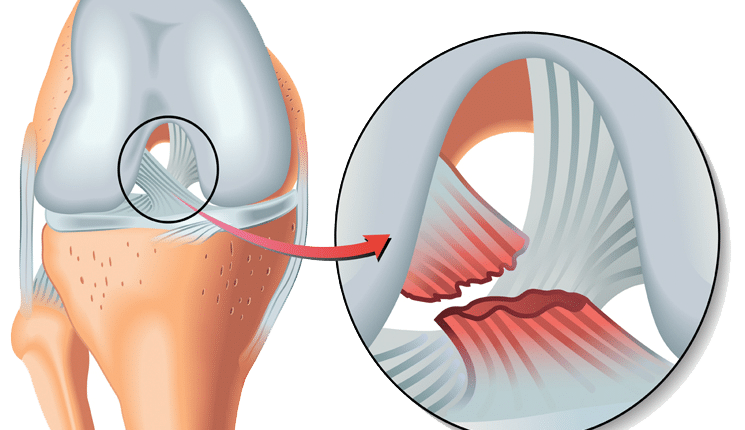

Ön çapraz bağ ameliyatı, dizdeki ön çapraz bağın (ÖÇB) yırtılması veya kopması durumunda yapılan cerrahi bir müdahaledir. Bu bağ, diz ekleminin stabilitesini sağlar ve sporcularda sıkça görülen bir yaralanma türüdür. Özellikle futbol, basketbol, kayak ve tenis gibi sporlarla uğraşan kişilerde ön çapraz bağ yaralanmaları daha yaygındır. ÖÇB’nin yaralanması, dizde şiddetli ağrıya, şişmeye ve dengesizliğe yol açar, bu da günlük aktiviteleri ve spor yapmayı zorlaştırır.